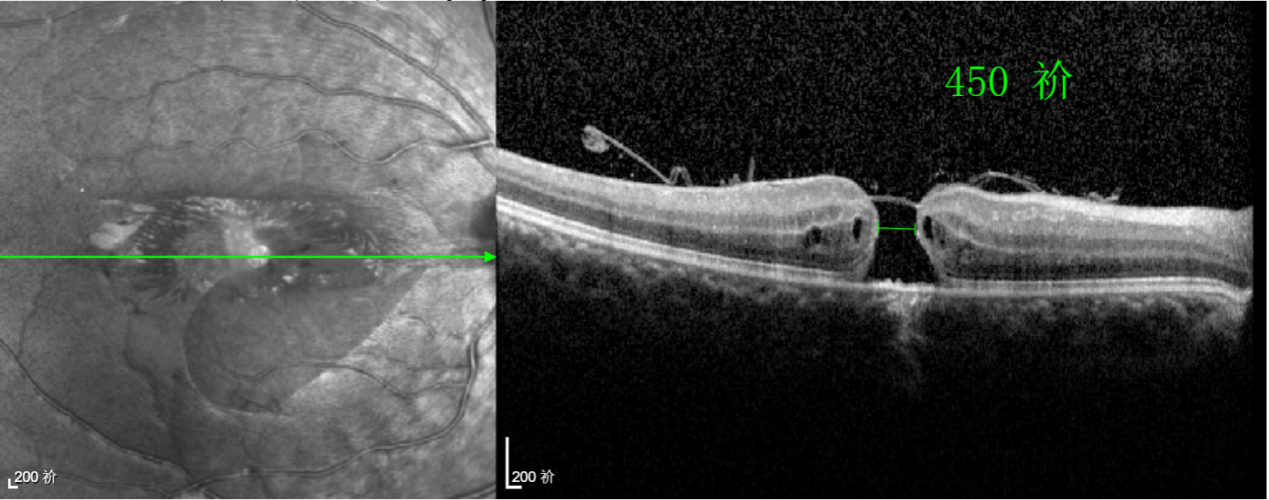

經(jīng)過詳細(xì)的檢查和評(píng)估,王曉波主任決定采用“內(nèi)界膜翻轉(zhuǎn)覆蓋聯(lián)合粘彈劑固定術(shù)”為誠誠進(jìn)行治療。

術(shù)中,醫(yī)生精細(xì)剝離黃斑區(qū)的內(nèi)界膜后,并非直接丟棄,而是巧妙地給它翻個(gè)面,讓它變成一塊天然“創(chuàng)可貼”,嚴(yán)密覆蓋在黃斑裂孔的表面。覆蓋的內(nèi)界膜像微型支架一樣撐住裂孔邊緣,防止它擴(kuò)大;同時(shí),這層膜本身含有能促進(jìn)生長的“養(yǎng)分”,能顯著刺激裂孔周圍的視網(wǎng)膜組織像爬山虎一樣快速生長、蔓延過來,最終把裂孔“補(bǔ)”好。

王曉波主任表示:該術(shù)式無需依賴硅油或氣體去頂壓裂孔促進(jìn)愈合,術(shù)后也就無需再保持俯臥體位,這不僅極大提升了患者的舒適度,更顯著提高了治療依從性。對(duì)于活潑好動(dòng)的兒童、難以長時(shí)間保持特殊體位的老年人,以及因其他健康問題無法耐受俯臥的患者而言,這項(xiàng)技術(shù)無疑帶來了巨大的便利和改善。

除此之外,利用自體組織覆蓋為黃斑裂孔提供了理想的愈合環(huán)境,裂孔閉合速度顯著快于傳統(tǒng)方法。誠誠接受手術(shù)24小時(shí)后,檢查可見內(nèi)界膜瓣位置良好;術(shù)后1個(gè)月,黃斑裂孔已經(jīng)閉合,視力恢復(fù)到0.5;術(shù)后兩個(gè)月,視力進(jìn)一步提升到0.7。